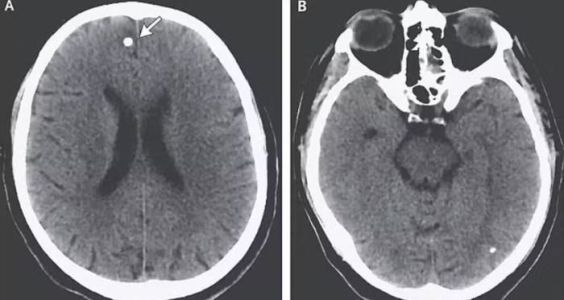

Os médicos, agora examinando seu cérebro mais de perto, encontraram diversas lesões preocupantes no órgão. Após questionamentos persistentes sobre sua dieta e hábitos, "TE" confessou aos médicos que consumia ovos de tênia que havia comprado online. A análise do que exatamente ela havia comprado revelou a presença de tênias pertencentes a duas espécies diferentes de parasitos.

Mas, os problemas no cérebro foram causados pelos ovos da outra espécie, chamada de Taenia Solium. Ela é comumente encontrada na carne de porco e libera pequenos ovos que, quando entram na corrente sanguínea, como foi o caso de "TE", se espalham para tecidos como músculos e cérebro levando a uma doença chamada de cisticercose.

Embora esses ovos não consigam eclodir fora do intestino, eles formam nódulos duros, semelhantes a cistos, que parecem caroços sob a pele. Hsu acrescentou ainda que há casos de alterações na visão, mudanças de personalidade e diminuição da função cognitiva devido à pressão exercida pelos nódulos e pelo inchaço do local, a depender do local em que se alojam no tecido do cérebro.

Os médicos deram a "TE" dois medicamentos para combater a infestação: um que paralisa os vermes, fazendo com que eles se desprendam do intestino, e outro que os priva dos açúcares necessários para sobreviverem. Eles também prescreveram esteroides para diminuir o nível de inflamação em seu cérebro e permitir que seu corpo eliminasse os ovos, embora isso não, fosse algo garantido.

Segundo os especialistas, após três semanas de internação, não havia mais sinais de ovos em seu cérebro e, seis meses depois, "TE" parecia não apresentar mais sintomas.